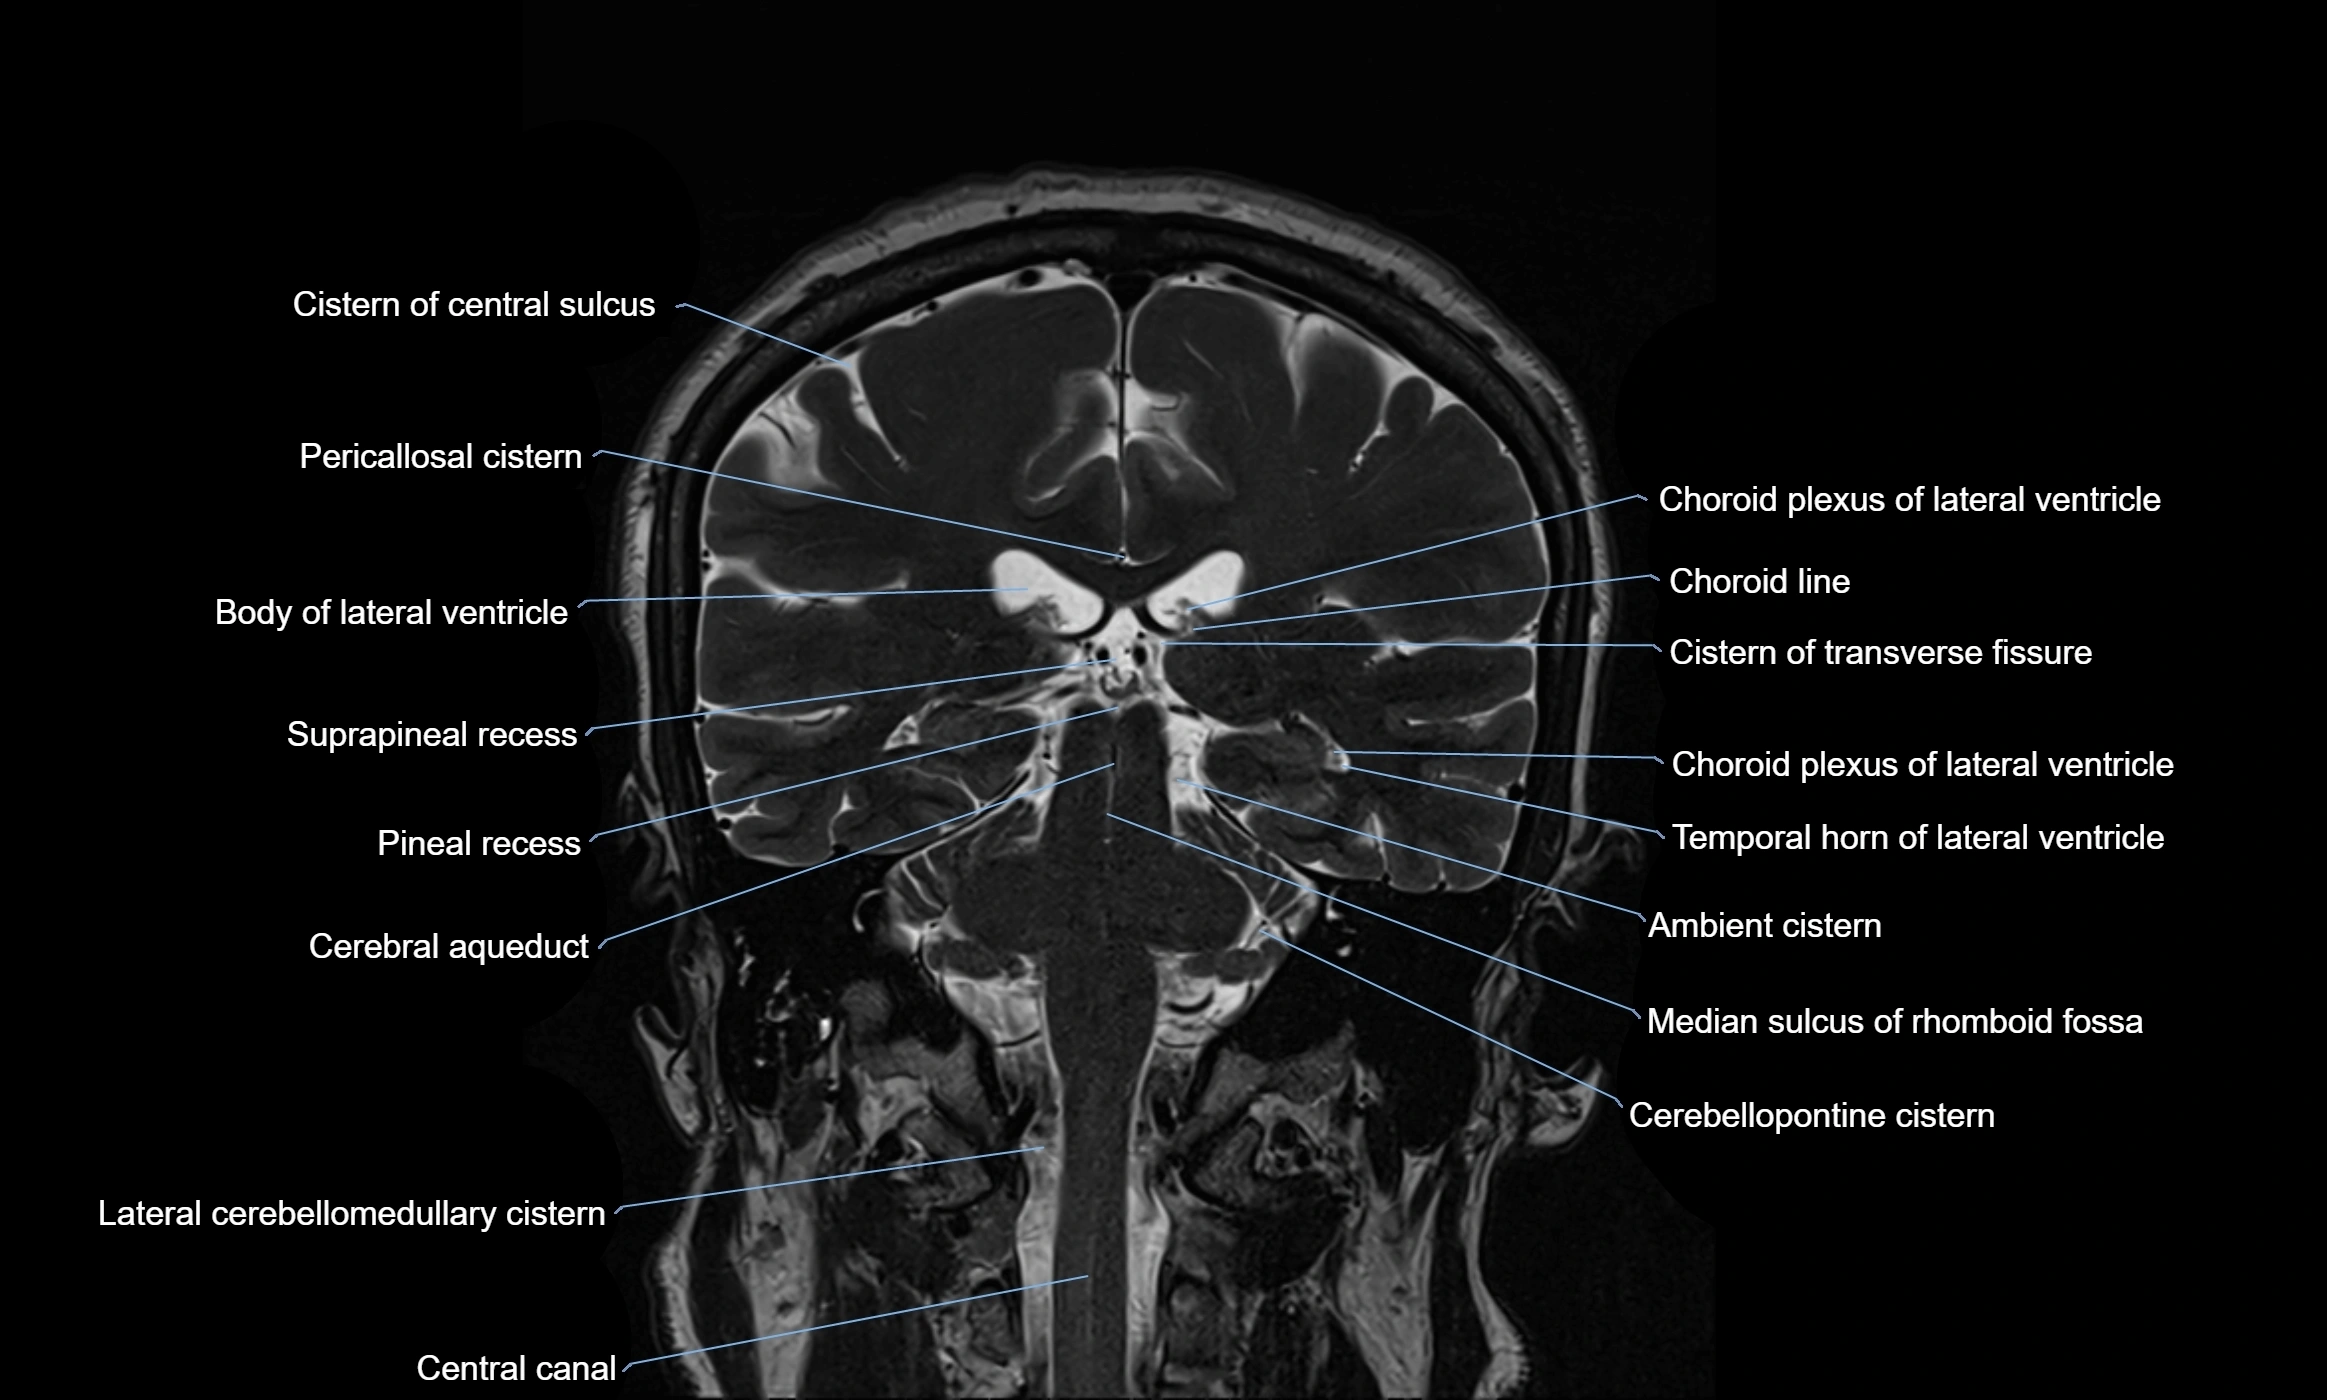

MRI images

image